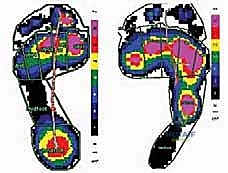

الشكل 1 • تشوهات القدم الجوفاء، منظر جانبي. لاحظ زيادة الانثناء الأخمصي لمقدمة ومنتصف القدم بالنسبة لمؤخرة القدم، وهو ما يسبب ضغطًا هائلاً على مشط القدم.

الشكل 2 • تشوهات القدم الجوفاء، منظر أمامي. يوضح مكونات انقلاب الكعب للداخل وتقوس مقدمة القدم، مما يؤدي إلى عدم استقرار الكاحل.